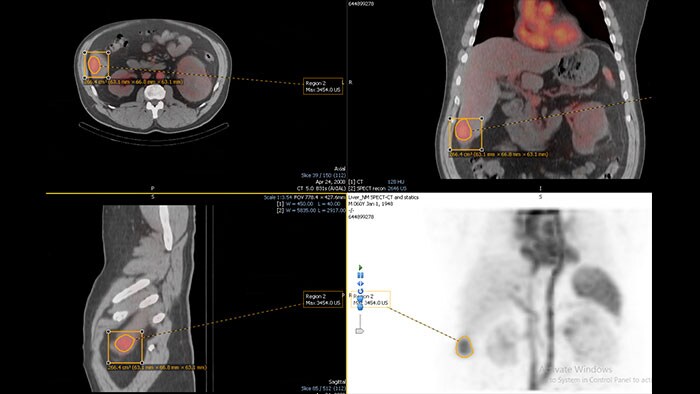

Enhanced user experience for NM reading with a leading NM viewing solution

A comprehensive NM solution, designed to enhance productivity of PET/CT and NM reading. It offers a solution for handling multiple studies requiring rigorous quantification of MV data**.

Benefits

* Mirada is a registered trademark of Mirada inc.

** Please contact local Philips representative for details on multivendor coverage.